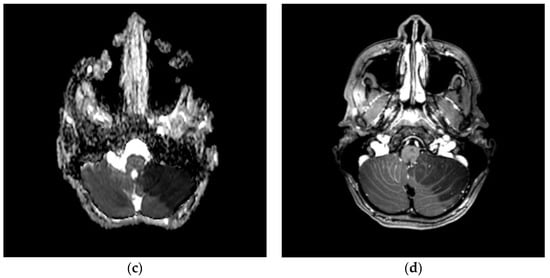

Brain CT scans, performed in 11 patients (9%), revealed alterations in two (1.6%). In the first case, a 12-year-old boy with headache, dizziness, diplopia, and ataxia, it revealed an extensive hypodensity of the left cerebellum and some hypodense spots in the thalami (Figure 2a); in the second one, a 10-month-old infant with MIS-C, with bulging anterior fontanelle and lethargy, it showed cerebral oedema and herniation.

Acute left cerebellar infarct in the distribution of the posterior inferior cerebellar artery (PICA) without mass effect and enhancement areas. Axial brain CT scan (a) and axial brain MRI images of DWI (b), ADC (c), and T1- WI after intravenous gadolinium contrast administration (d) sequences.

Brain or spinal cord MRI, performed in 12 patients (9.8%), was altered in five (4.1%). In the above-mentioned 12-year-old boy, it showed an ischemic injury of the left cerebellum cortex (Figure 2b–d), and the left posterior inferior cerebellar artery (PICA) was unrecognizable in the angiographic sequences. Multiple thalamic ischemic injuries were found also in a 15-year-old boy with confusion and loss of consciousness. In the patient with GBS, the spinal cord MRI showed contrast enhancement of cauda equina roots. In the 10-month-old infant with MIS-C and cerebral oedema on CT, mild cerebral atrophy and areas of altered signal were revealed at MRI performed 2 weeks after the CT scan. In a two-year-old boy with MIS-C and impairment of consciousness, a second MRI, performed after one month from the clinical onset, showed diffuse cortical and subcortical brain atrophy. The three patients with stroke underwent cerebral DSA, which was normal in all but the boy with the cerebellar stroke. The instrumental data are shown in Table 3.

Three patients were diagnosed with AIS during the COVID-19. A 12-year-old boy had a left cerebellar stroke (Figure 2) due to PICA occlusion with a complete clinical recovery but partial radiological improvement. The second was a 15-year-old boy with consciousness impairment and bilateral thalamic ischemic lesions. Despite a clinical improvement, a one-month control brain MRI showed a new cortex ischemic injury. At discharge, his neurological impairments improved with persistent confusion episodes. The third was a six-year-old girl who presented a right central retinal artery occlusion (CRAO) together with an idiopathic contralateral optic neuropathy (Figure 3). Neuroimaging (brain CT, MRI, and angiography) was normal. She completely lost her right eye function, but she recovered her fingers counting on the left.